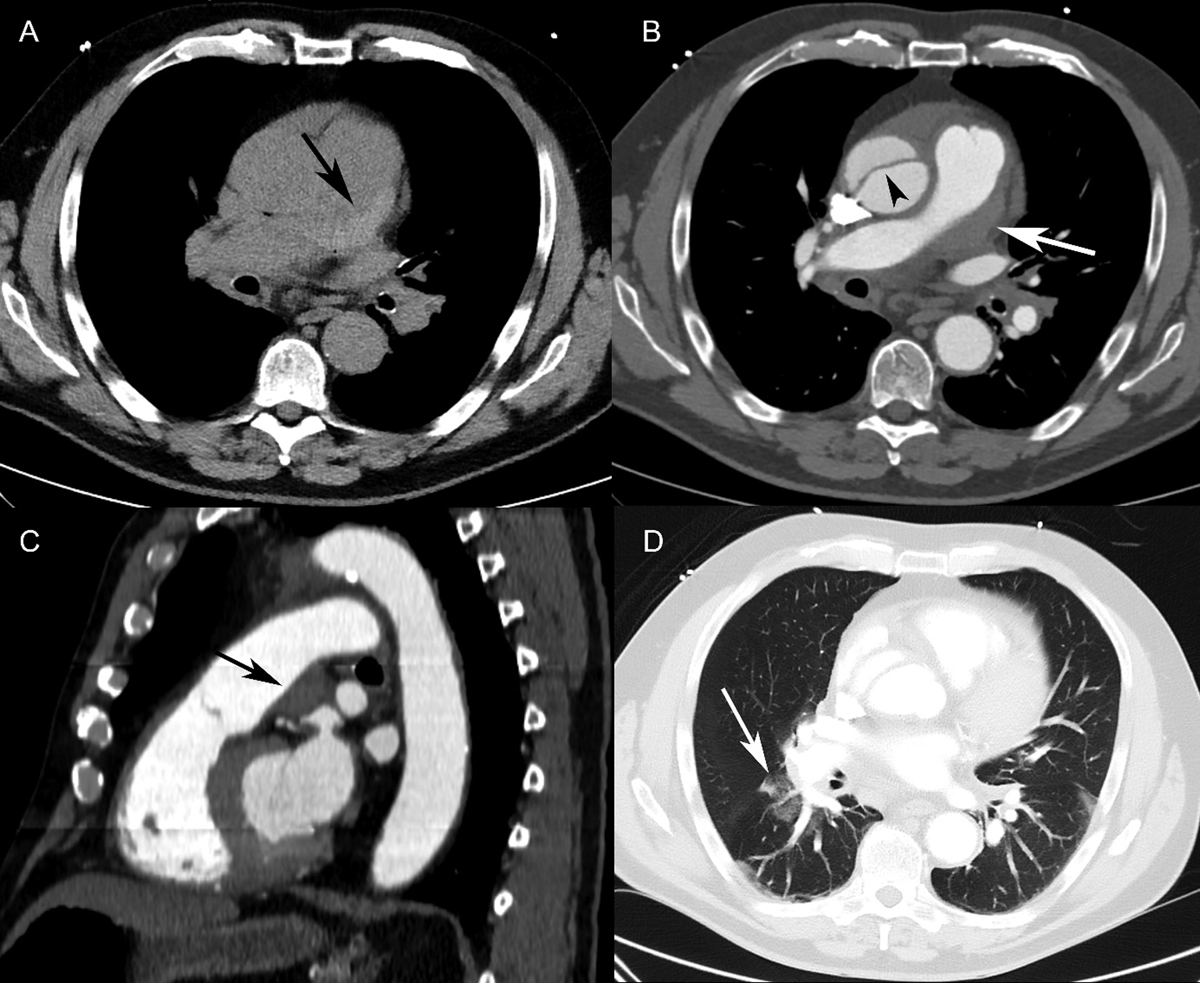

Figure 2

Patient 2. (A) Axial non-contrast-enhanced CT showed a hyperdense lesion along the pulmonary trunk wall (black arrow). (B) Contrast-enhanced CT (axial view) revealed an eccentric hypodense defect in the pulmonary trunk (white arrow), mimicking a mural thrombus. The intimal flap was seen in the ascending aorta (arrowhead). (C) Sagittal reformatting of a contrast-enhanced CT scan revealed a lesion with well-defined margins at an obtuse angle (black arrow) along the pulmonary trunk wall, resulting in a slight narrowing of the pulmonary trunk lumen. This was not enhancing, suggestive of an intramural hematoma. (D) Axial CT (lung window) showed patchy ground-glass opacities in the right lower lobe around the segmental pulmonary arteries, consistent with alveolar hemorrhage.

Figure 3

Patient 3. (A) Non-contrast-enhanced CT showed circumferential high attenuation along the walls of the main and right pulmonary arteries, consistent with pulmonary artery intramural hematoma (white arrowheads). Stanford type A aortic dissection with an intimal flap in the ascending aorta was also seen (black arrowhead). (B) Non-contrast-enhanced CT revealed an intimal flap of the thoracic aorta (black arrowhead) and displacement of atherosclerotic calcifications into the aortic lumen (white arrowhead).